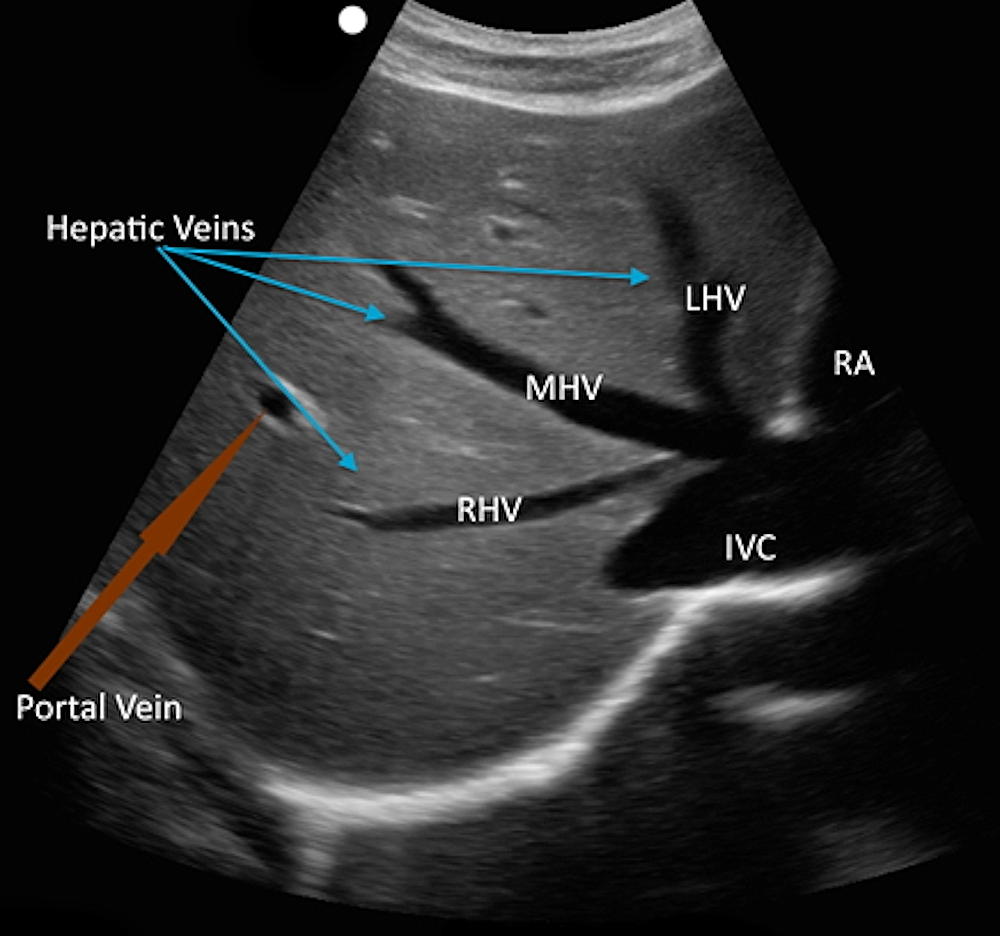

The convergence of the hepatic veins creates the characteristic “white star” appearance, marking the confluence with the inferior vena cava in the midline (Figure 1).